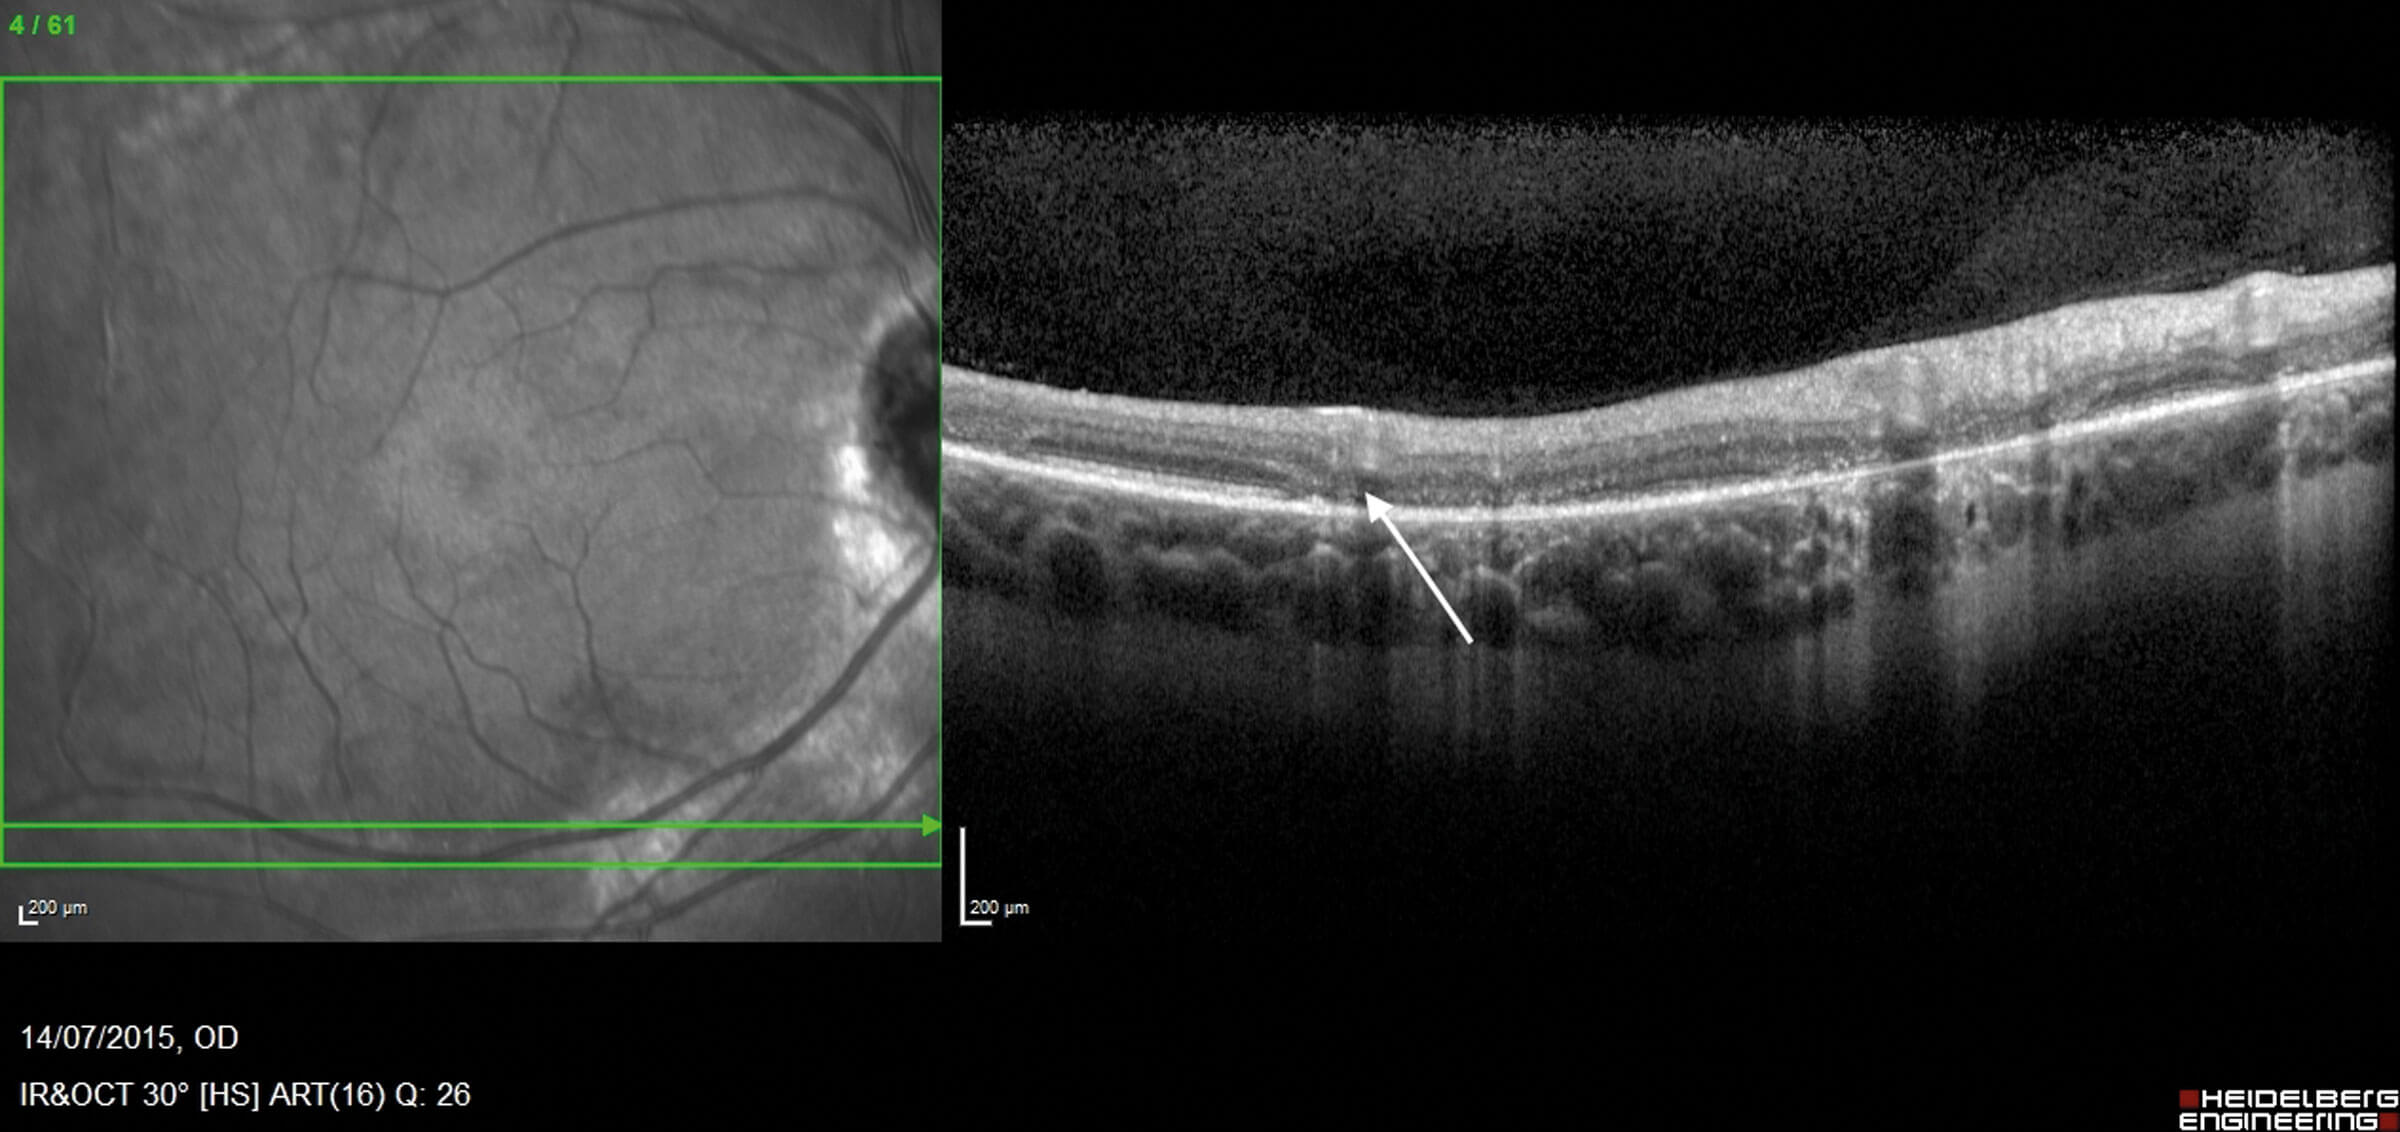

Figure 3: OCT through the retinal vasculature demonstrating thinning

of the outer retina and loss of the ellipsoid zone (white arrow).

In human eyes, descriptions of histopathological change are based on multimodal imaging techniques including spectral-domain-OCT (SD-OCT) and fluorescein angiography (FFA), as well as visual electrophysiology. In a retrospective study by Lee, et al., SD-OCT imaging of retinochoroidal atrophic areas in PPRCA showed thinning of the outer nuclear layer (ONL), external limiting membrane (ELM), ellipsoid zone (EZ) and interdigitation zone (IZ) band. Reduced choroidal thickness is another feature even in the absence of RPE atrophy. Pigmented paravenous retinochoroidal atrophy also appears to primarily affect choroidal vasculature as evidenced by findings in keeping with choriocapillaris hypoperfusion on OCT angiography, with relative sparing of the retinal capillary plexuses [12]. Macula may be involved and this is characterised by disruptions of the EZ, IZ, and RPE, as well as choroidal thinning [10,12].

Optical coherence tomography

Optical coherence tomography findings include absent EZ and ELM, thinning of ONL and outer plexiform layer, partial preservation of RPE, and choroidal thinning. Retinal nerve fibre layer and GCL can also be thin, and in cases with macular atrophy, thinning of all retinal layers may be present [17]. Pigment clumps appear as hyper-reflective plaques with underlying shadowing [15]. Optical coherence tomography angiography findings are characterised by vascular impairment, especially at the level of deep capillary plexus [17].